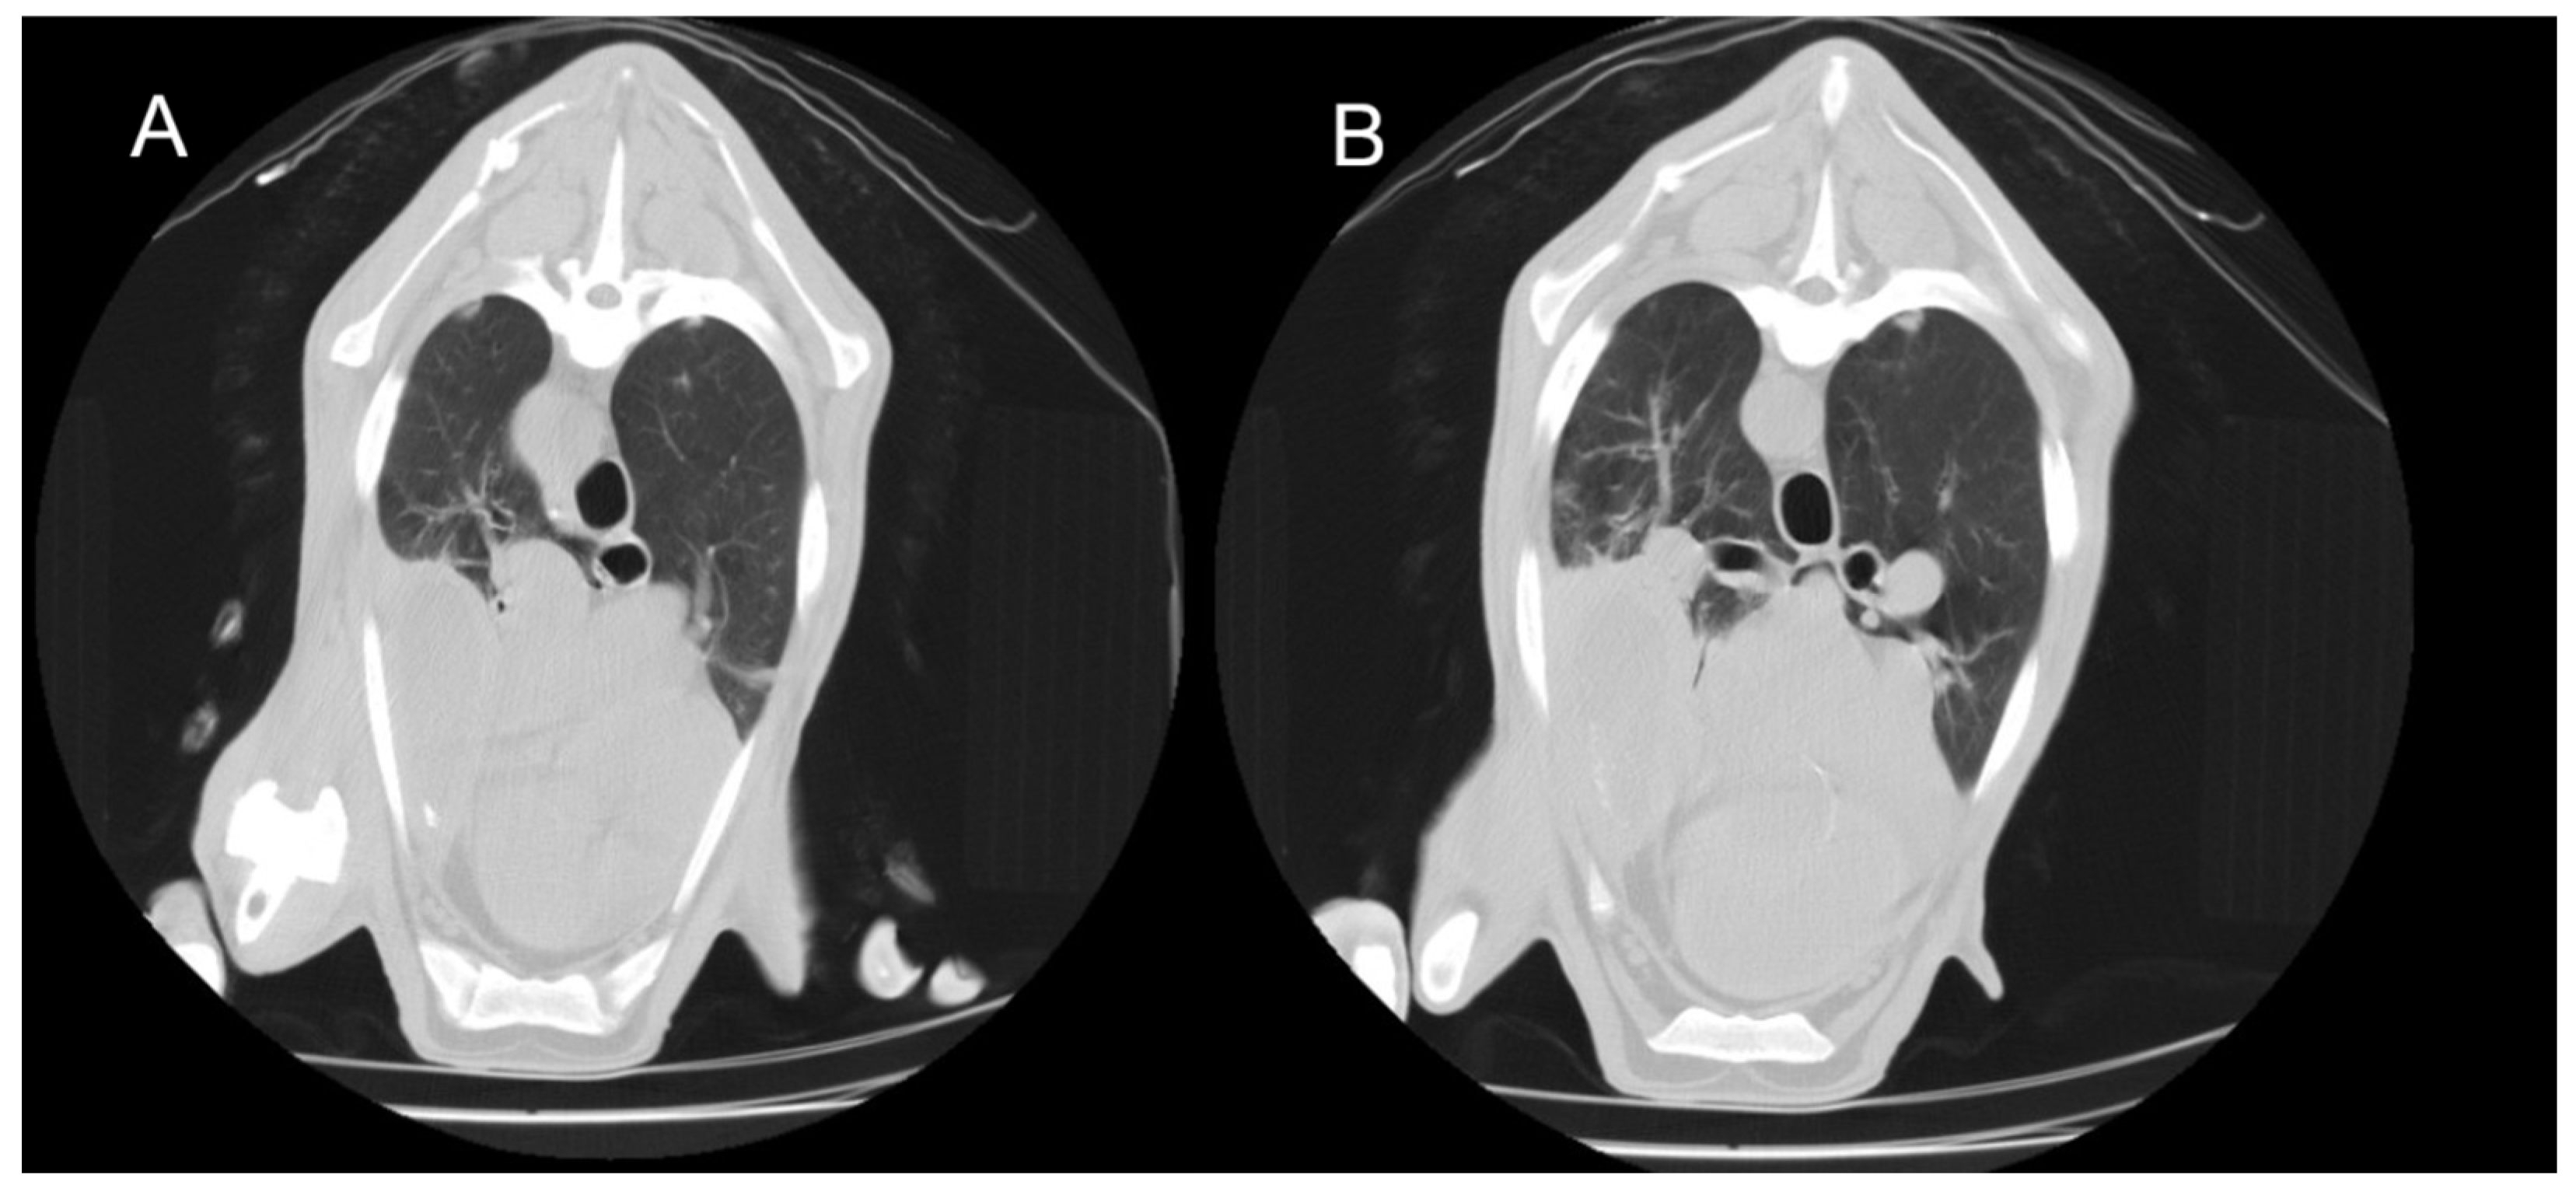

3.3.1. Interstitial Pneumonia (SRLV)

3.3.2. Gangrenous Pneumonia (GN)

3.3.3. Chronic Form of Ovine Respiratory Complex (ORC)